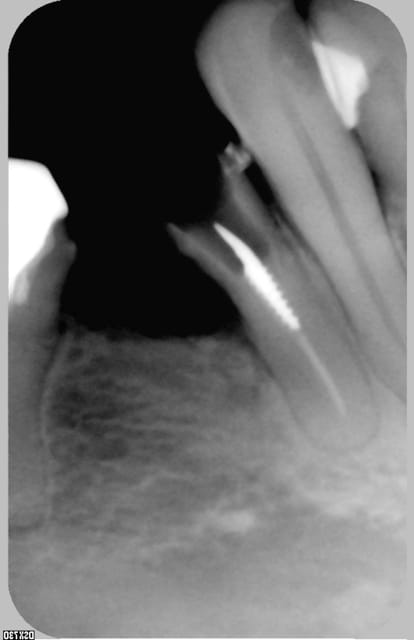

si la fraise est assez longue pour que la tete de turbine ne bloque pas sur 34-36, et si on reste bien dans l'axe....

pour masseran c'est cela, sur une 35 en plus, avoue qu'on te gate!!!!

bin , c'etait juste pour rendre service a phical que j'ai desobturé la dent et cassé puis aleser un peu le screw post, suis serviable moi madame...

oui la dent est toujours là, inlaycore et coiffe, classique et sans rien de special